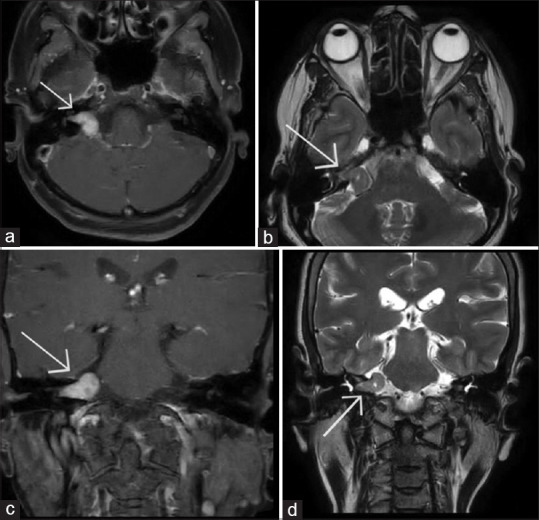

Methods: This retrospective study was carried out on 85 patients with HFS, presenting at a tertiary eye care center in South India. Demographic and clinical details were recorded for all patients. Of these, the patients who had undergone magnetic resonance imaging (MRI) of the brain were analyzed for primary and secondary HFS.

Results: The mean age of the patients was 56.11 ± 12.51 years. The age at onset of HFS was 54.9 ± 12.7 years. The disease duration was 9.51 ± 7.28 years. Male:female ratio was 1:1.17. The right side was involved in 31 patients (36.47%) and the left side in 54 patients (63.52%). MRI was performed in 54 (63.52%) patients and showed neurovascular conflict in 22 (40.74%) patients and space-occupying lesions in 2 (3.70%) patients. Forty-nine (57.64%) patients had primary HFS, while five (5.88%) patients had secondary HFS due to old facial palsy in 3 and space-occupying lesions in two patients. Twenty (23.52%) patients received botulinum toxin A with a good response. Type of HFS had a significant association with hypertension (P = 0.046) while no significant association was present between laterality of HFS and systemic diseases (P > 0.05 each). Multivariate analysis showed a marginally significant association between type of HFS and hypertension (P = 0.057).